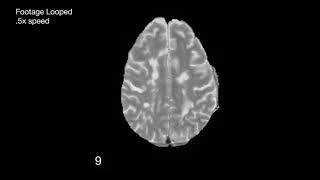

Time-lapse MRI From a Patient With MS and Expanding Rim Lesions

This time-lapse video, constructed from 10 coregistered intensity normalized axial MRI scans (proton density [PD] sequence) obtained over 7 years from a ...

Time-lapse MRI From a Patient With MS Showing an Expanding Rim+ and a Shrinking Rim− Lesion

This time-lapse video, constructed from 118 coregistered intensity normalized MRI scans (proton density [PD] sequence) obtained over 29 years (average, ...